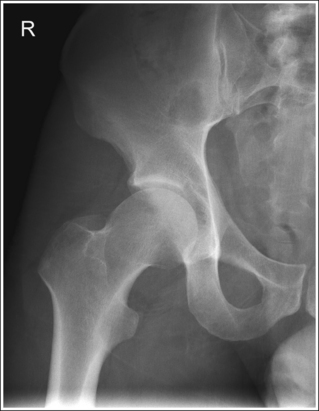

• Poor leg positioning. The relationship of the patient's leg to the imaging table determines how the femoral neck and trochanters are shown on an AP hip projection. In general, when patients are relaxed, their legs and feet are externally (laterally) rotated. On external rotation, the femoral neck declines posteriorly (toward the table) and is foreshortened on an AP hip projection. Increased external rotation increases the degree of posterior decline and foreshortening of the femoral neck on the image. If the patient's leg is externally (laterally) rotated enough to position the foot at a 45-degree angle and an imaginary line connecting the femoral epicondyles at a 60- to 65-degree angle with the imaging table, the femoral neck is demonstrated on end and the lesser trochanter is demonstrated in profile (Figure 7-5; see Image 3). If the patient's leg is positioned with the foot placed vertically and an imaginary line connecting the femoral epicondyles at approximately a 15- to 20-degree angle with the imaging table, the lesser trochanter is demonstrated in partial profile and the femoral neck is only partially foreshortened (see Image 4).

IMAGE 3

IMAGE 4

The femoral neck is completely foreshortened, and the lesser trochanter is demonstrated in profile. The patient's leg was in external rotation with the foot positioned at a 45-degree angle and the femoral epicondyles at a 25- to 30-degree angle with the imaging table, as shown in Figure 7-5.

Internally rotate the patient's leg until the foot is angled 15 to 20 degrees from vertical and the femoral epicondyles are positioned parallel with the imaging table, as shown in Figure 7-4.

The femoral neck is partially foreshortened, and the lesser trochanter is demonstrated in profile. The patient's leg was externally rotated, bringing the foot vertical and the femoral epicondyles to approximately a 15- to 20-degree angle with the imaging table.